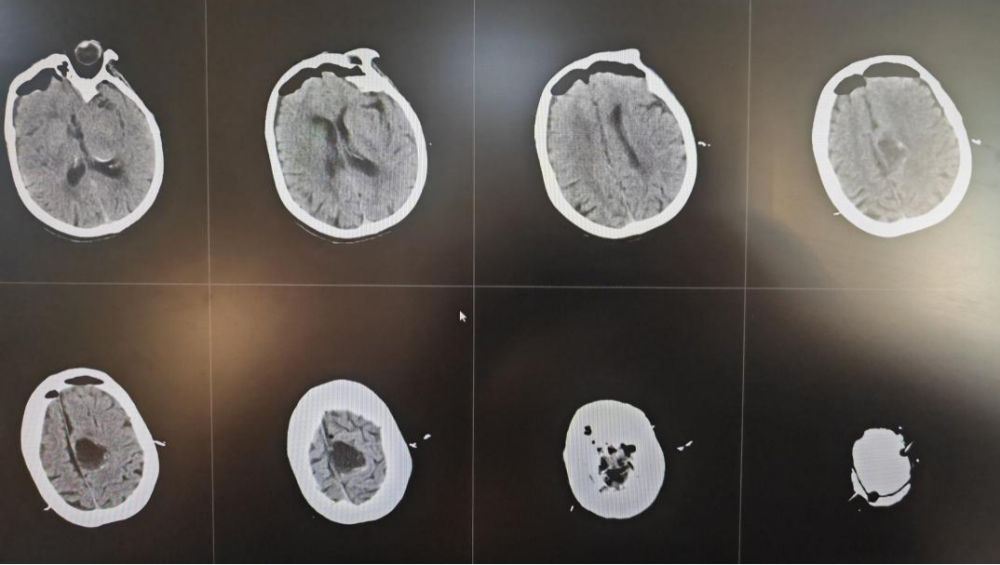

术前MRI

术后CT

术后,患者很快苏醒,四肢肢体肌力无下降,感觉及运动良好,语言流利,手术圆满成功。术后第二天,张大娘即能下床活动锻炼,术后复查CT提示肿瘤全切。病理结果回报提示:脑膜瘤(WHO分级1级)。经过我院神经外科二病区医护团队的精心护理和治疗,患者恢复良好,头部伤口愈合良好,如期拆线,目前已康复出院。“做完手术我头就不疼了,感觉看东西也清楚了,手术第二天我就开始在医生和护士的指导下锻炼,现在觉得自己特别轻松,你们的医生技术好,护士也耐心,真的都是好样的!”出院时张大娘高兴地说。